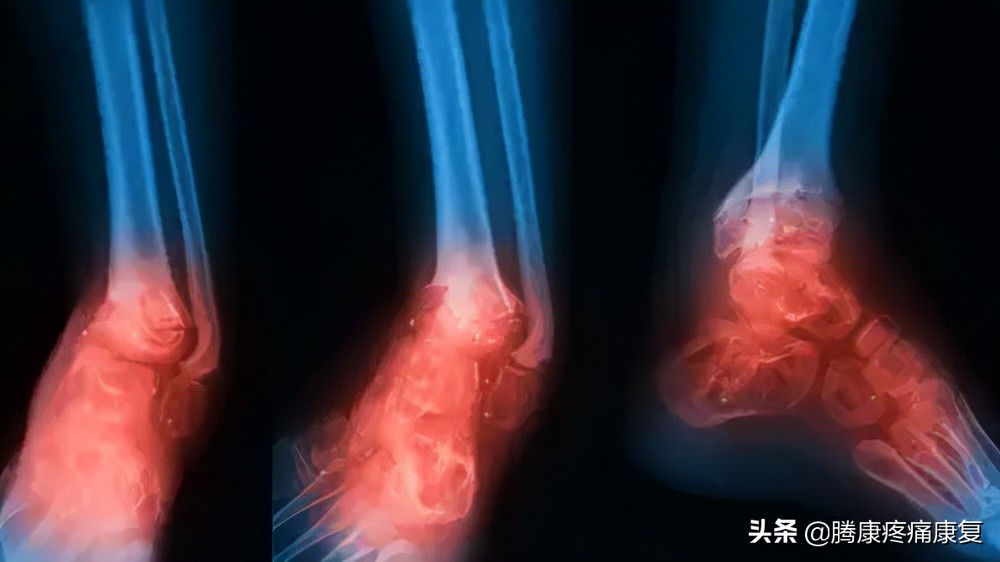

小腿骨折

小腿的胫骨或腓骨骨折可能是由于摔倒或腿部外伤性打击(如车祸)引起的。

老人小腿疼痛是什么原因,小腿疼痛是什么原因引起的

这种损伤可能导致严重的小腿疼痛,肿胀,行走困难或无法承受任何重量。